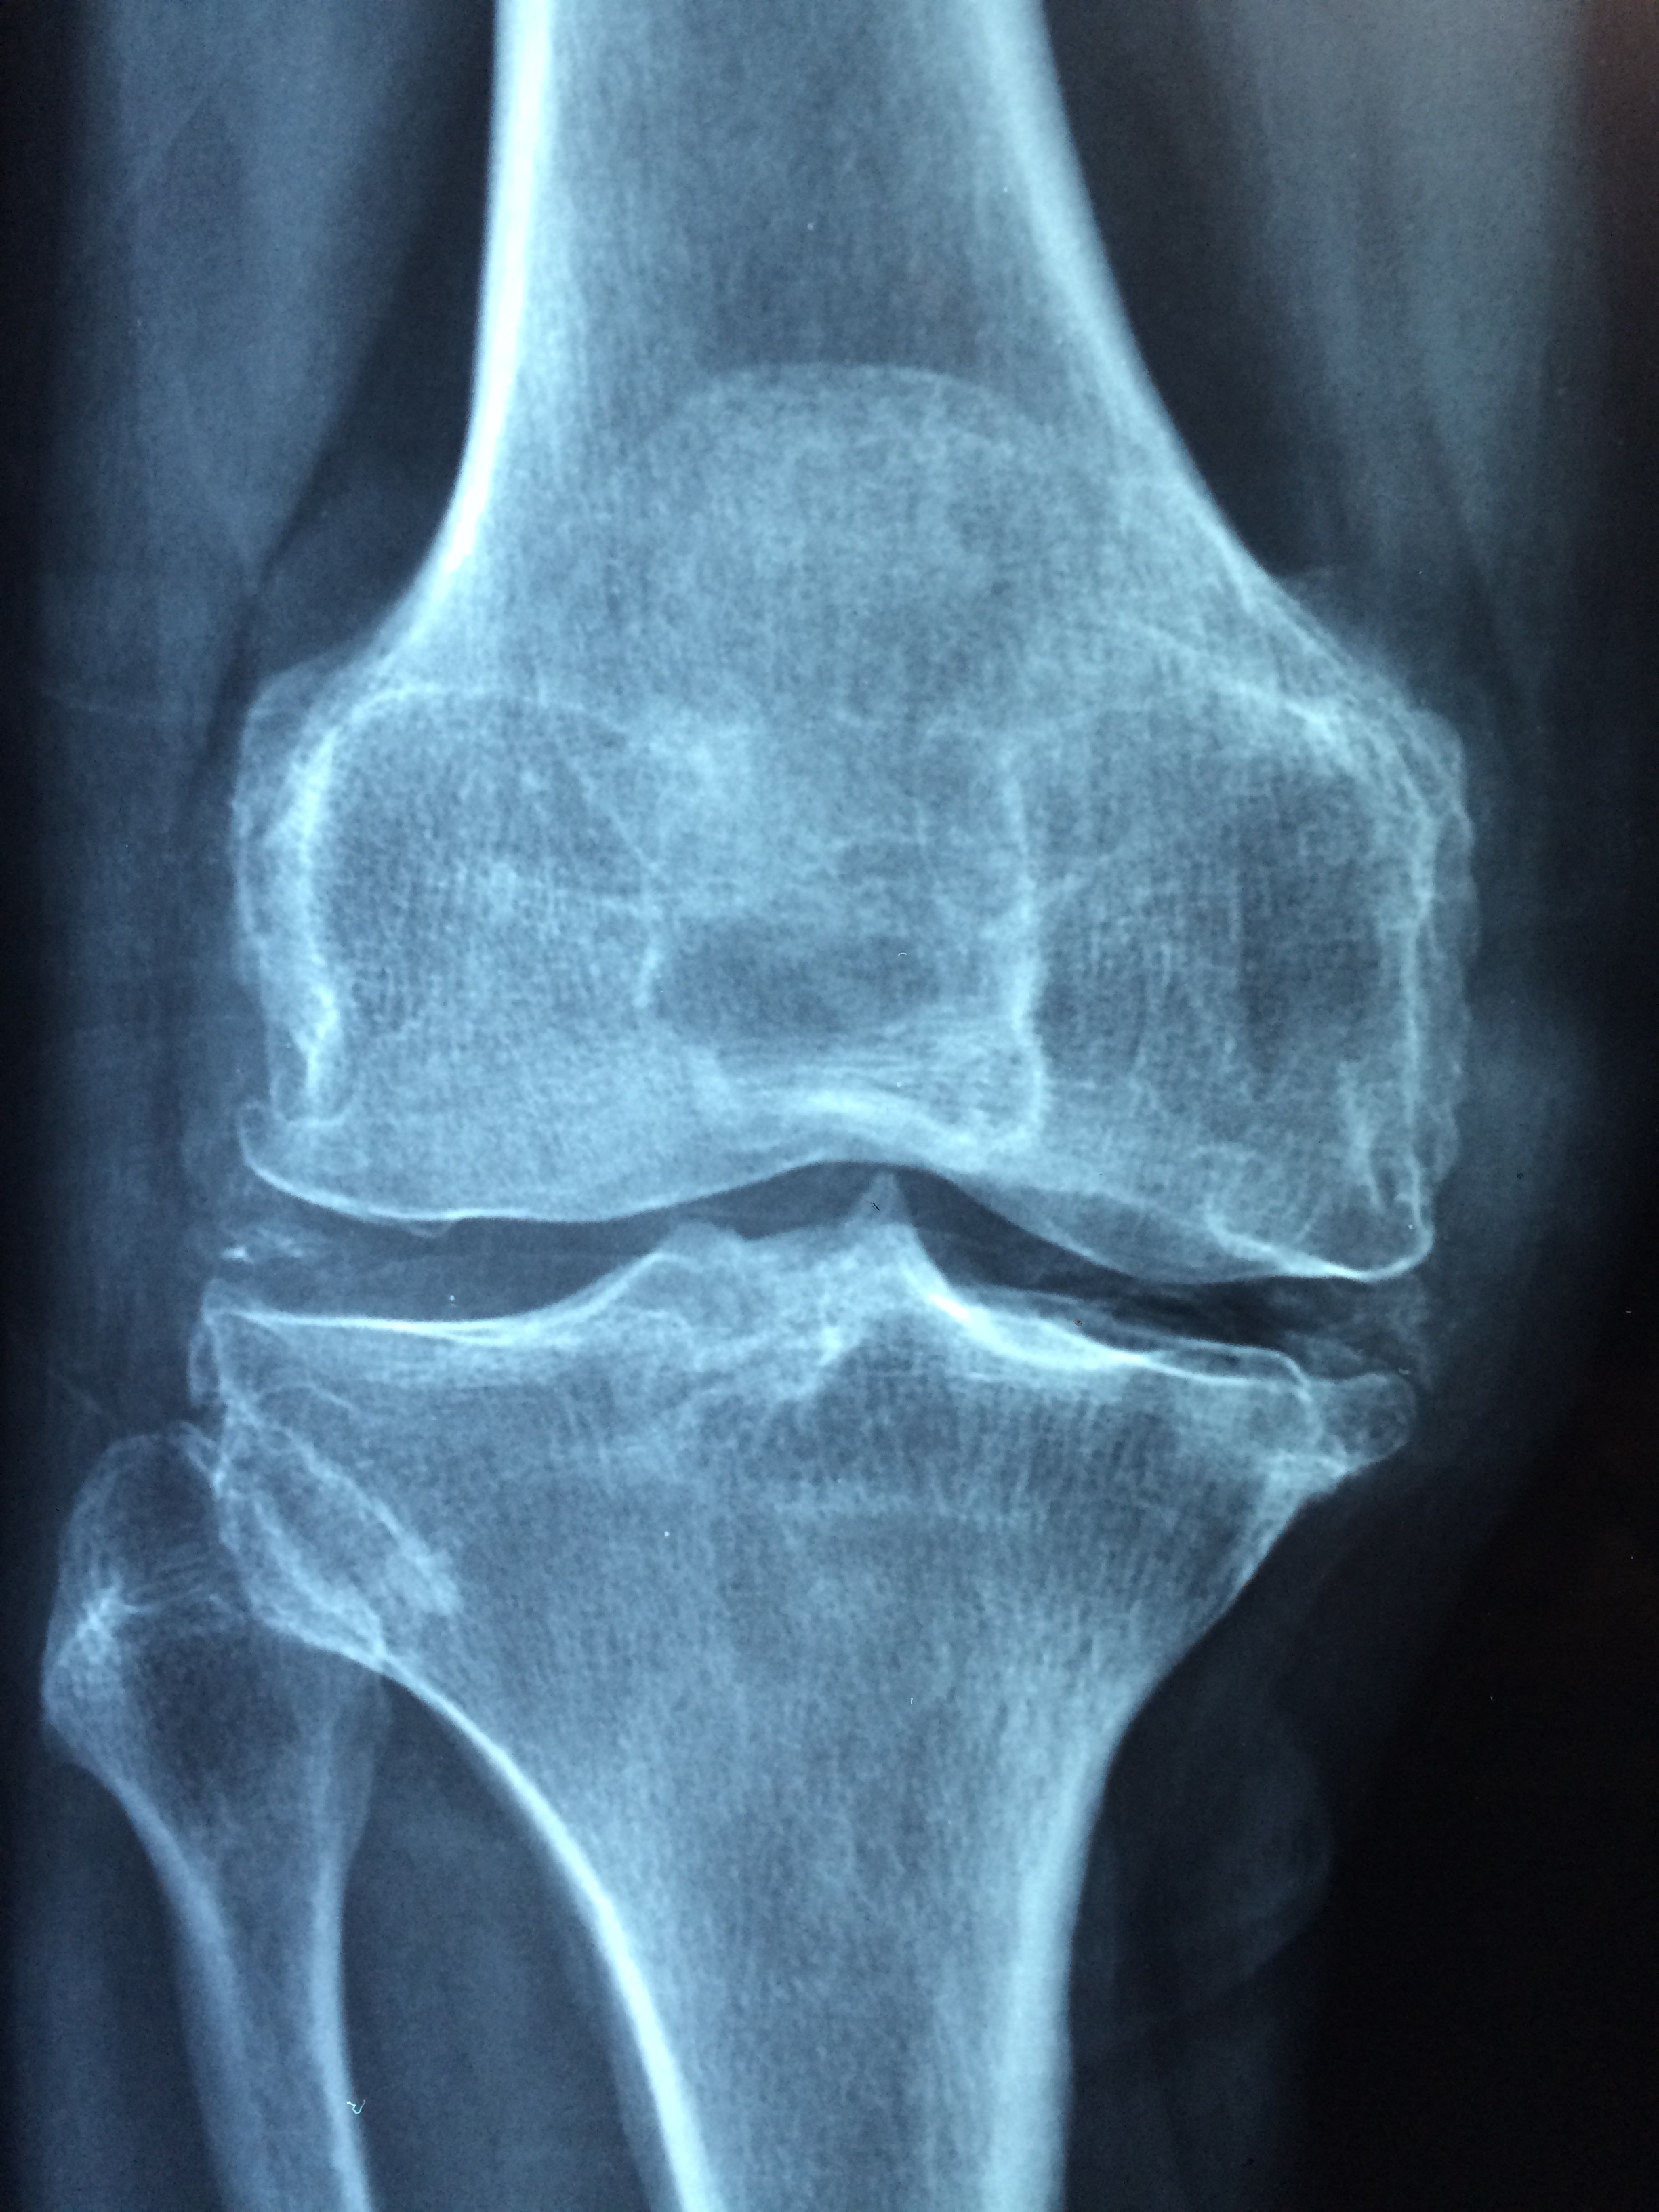

관절염은 관절에 통증, 경직 및 염증을 유발하는 전 세계 수백만 명에게 영향을 미치는 일반적인 질환입니다. 관절염은 종종 노화와 관련이 있지만 발병을 예방하거나 지연시키기 위해 취할 수 있는 조치가 있습니다. 건강한 습관을 채택하고 생활 방식을 변경함으로써 관절염 발병 위험을 줄이고 최적의 관절 건강을 유지할 수 있습니다. 이 가이드에서 우리는 관절염 예방을 위한 효과적인 전략을 탐색하고 관절 건강과 전반적인 웰빙을 통제할 수 있도록 힘을 실어줍니다.

건강한 체중 유지 관절염을 예방하는 가장 중요한 요소 중 하나는 건강한 체중을 유지하는 것입니다. 과도한 체중은 관절, 특히 무릎, 엉덩이 및 척추와 같은 체중을 견디는 관절에 추가적인 스트레스를 가하여 관절염 및 관절 손상의 위험을 증가시킵니다. 균형 잡힌 식단과 규칙적인 운동을 통해 건강한 체중을 유지함으로써 관절에 가해지는 부담을 줄이고 마모로부터 관절을 보호할 수 있습니다. 과일, 야채, 통곡물, 기름기가 많은 단백질 및 건강한 지방을 포함한 다양한 영양소가 풍부한 식품 섭취에 집중하고 설탕이 많이 첨가된 가공 식품, 설탕이 함유된 간식 및 음료를 제한합니다. 걷기, 수영, 사이클링 또는 근력 운동과 같은 규칙적인 신체 활동을 일상에 통합하여 체중 관리를 지원하고 관절 주변 근육을 강화합니다. 체중 관리를 우선시함으로써 관절염 발병 위험을 현저히 낮추고 나이가 들면서 더 나은 관절 건강을 누릴 수 있습니다.

규칙적인 신체 활동은 관절 건강을 유지하고 관절염을 예방하기 위해 필수적입니다. 운동은 관절 주변의 근육을 강화하고 유연성과 운동 범위를 개선하며 경직과 통증을 줄이는데 도움이 됩니다. 일주일에 2일 이상 근육 강화 활동과 함께 최소 150분의 중간 강도의 유산소 활동 또는 75분의 격렬한 활동을 목표로 합니다. 걷기, 수영, 사이클링, 요가 또는 태극권과 같이 관절에 부드러운 활동을 선택하고 체력 수준이 향상됨에 따라 점차적으로 강도와 지속 시간을 증가시킵니다. 스트레칭 운동을 일상 생활에 포함시켜 유연성을 향상시키고 부상 위험을 줄입니다. 기존의 관절 통증이나 관절염이 있다면 물리 치료사 또는 공인 트레이너와 협력하여 필요와 능력에 맞는 개인화된 운동 계획을 개발하십시오. 활동적이고 규칙적으로 운동함으로써 관절을 건강하게 유지하고 관절염 관련 합병증의 위험을 줄일 수 있습니다.

관절을 덮고 좋은 자세를 유지하세요 관절을 덮고 좋은 자세를 유지하는 방법을 취하는 것도 관절염을 돕고 일반적인 통증과 경직을 줄이는데 도움이 될 수 있습니다. 무거운 물체를 들어 올리거나 충격이 큰 스포츠를 하는 것과 같이 관절에 과도한 부담을 주는 반복적인 움직임이나 컨디셔닝을 피하십시오. 물체를 들어 올리거나 운반할 때 적절한 신체 역학을 사용하고 오래 앉아 있거나 서 있는 동안 휴식을 취하고 스트레칭을 하세요. 어깨를 뒤로 젖히고 턱을 정렬하여 똑바로 앉고 일어서서 좋은 자세를 유지하세요. 특히 평평한 바닥이나 높은 굴곡이 있는 경우에는 프로보티브 신발과 정형외과 삽입물을 사용하여 바닥과 발목을 완충하고 지지하세요. 작업을 하거나 주행 중에 관절에 가해지는 부담을 줄이기 위해 인체공학적 캐비닛 워크와 의상에 투자하세요. 관절을 덮고 좋은 자세를 유지하기 위해 선견지명을 취함으로써 관절염의 위협을 최소화하고 더 나은 일반적인 건강과 이동성을 즐길 수 있습니다.